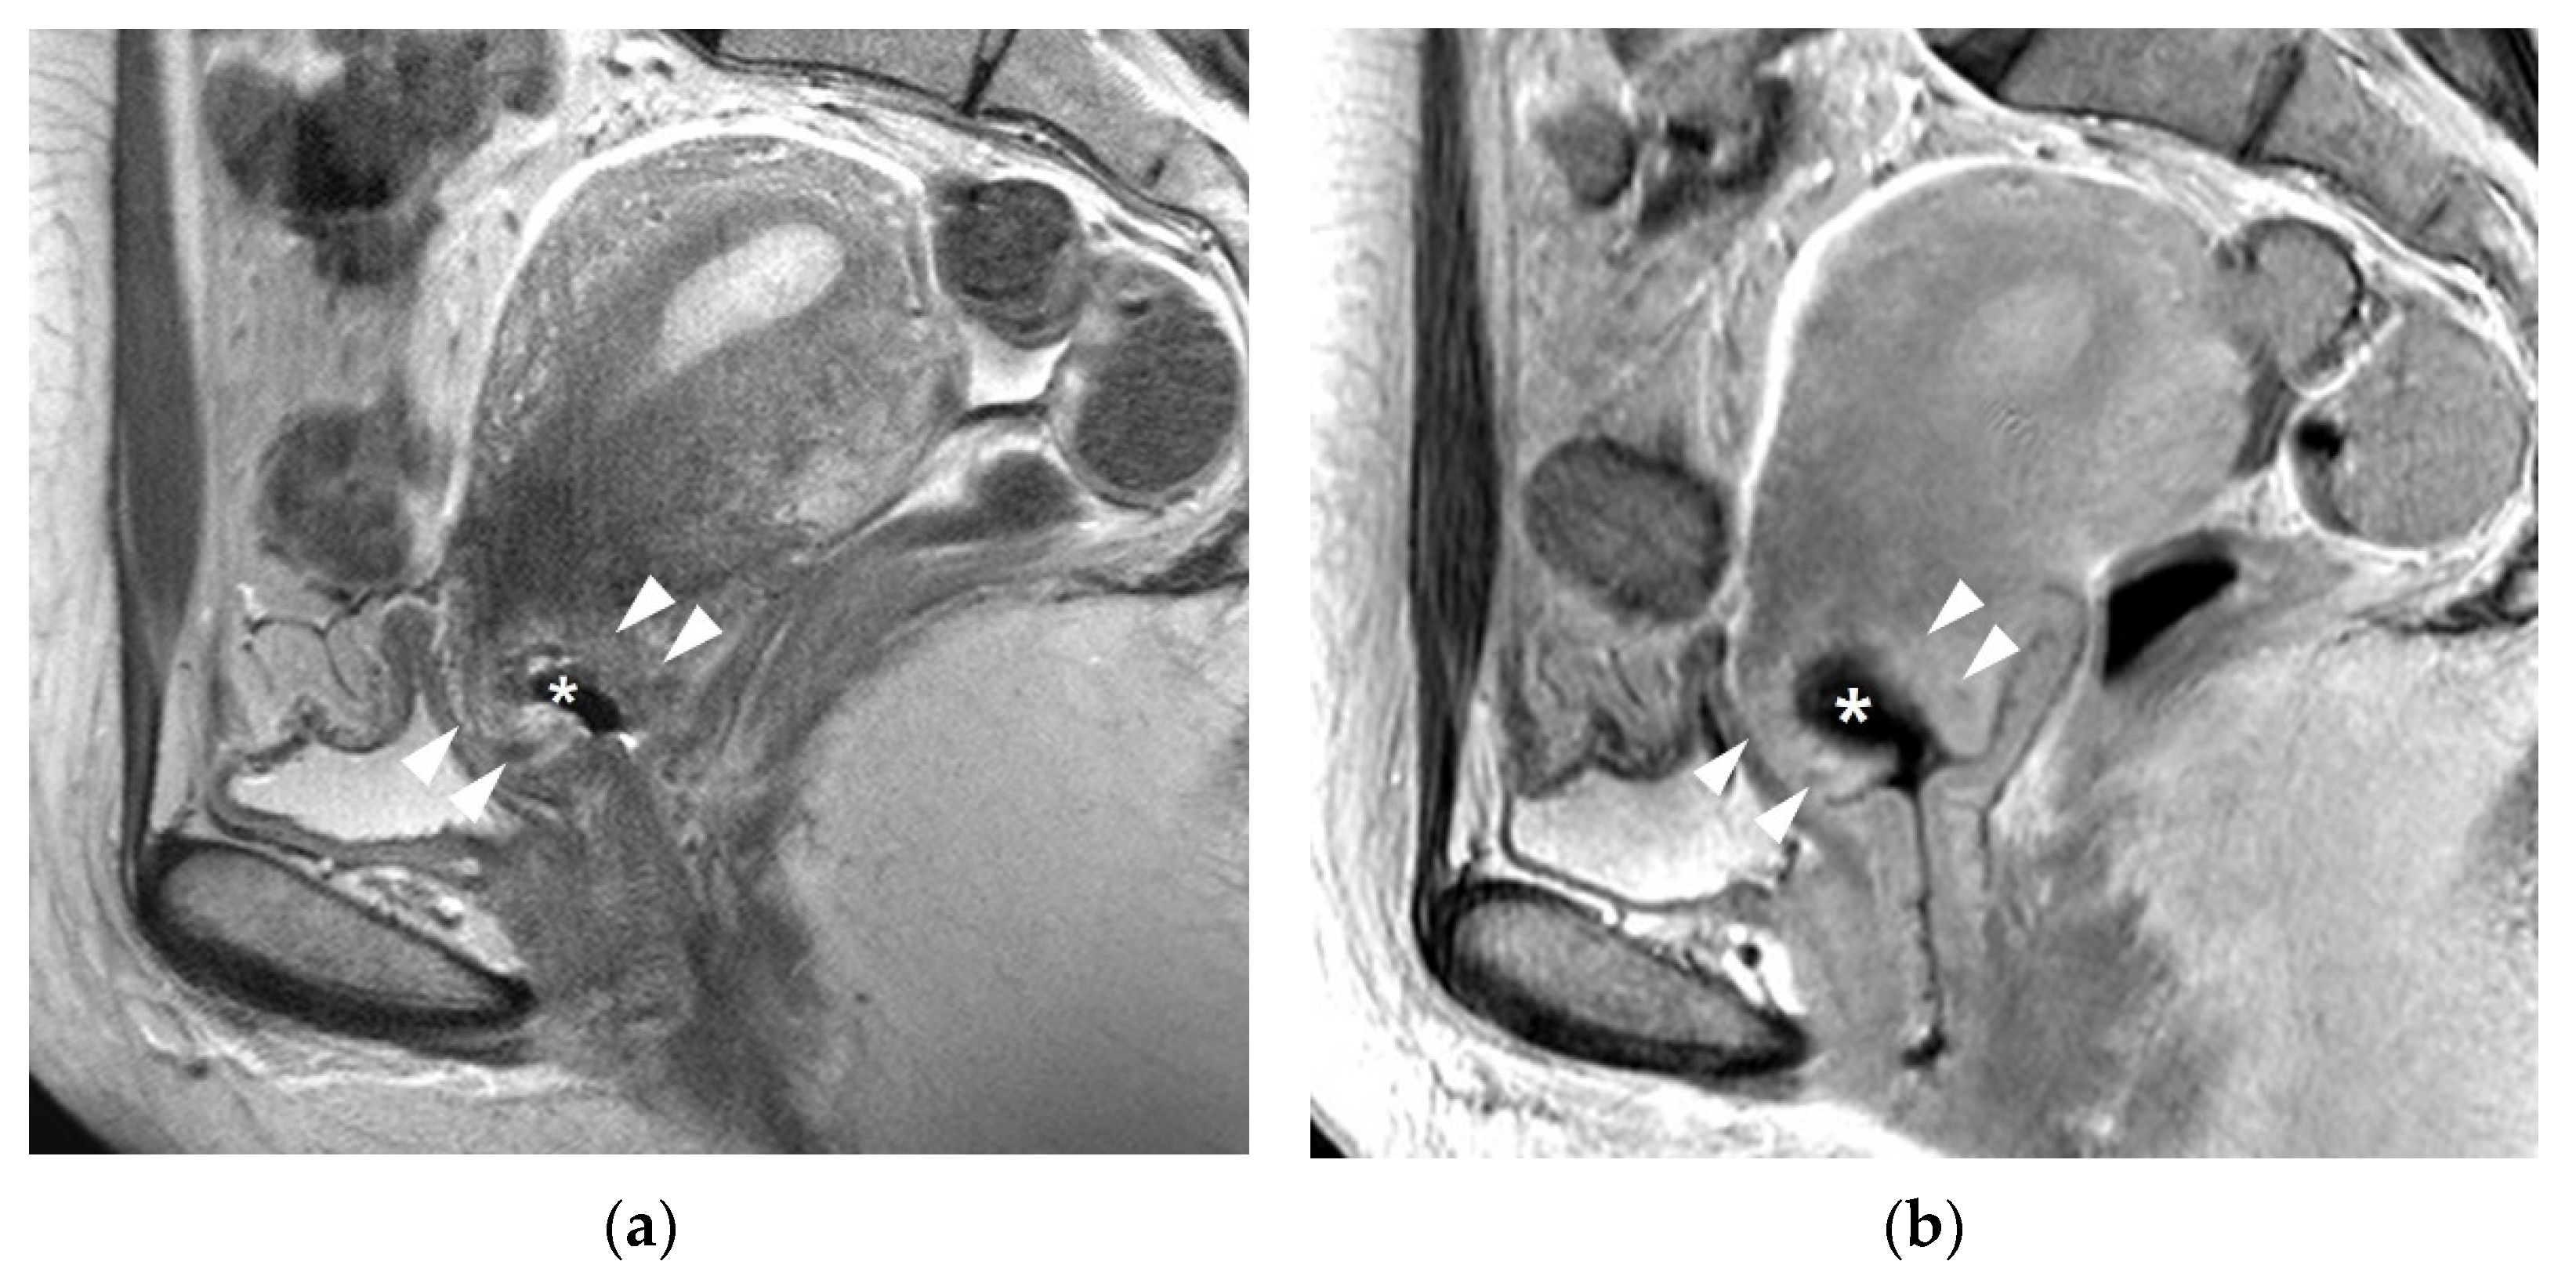

3.1. T2WI Findings

4. Post-Conization MRI